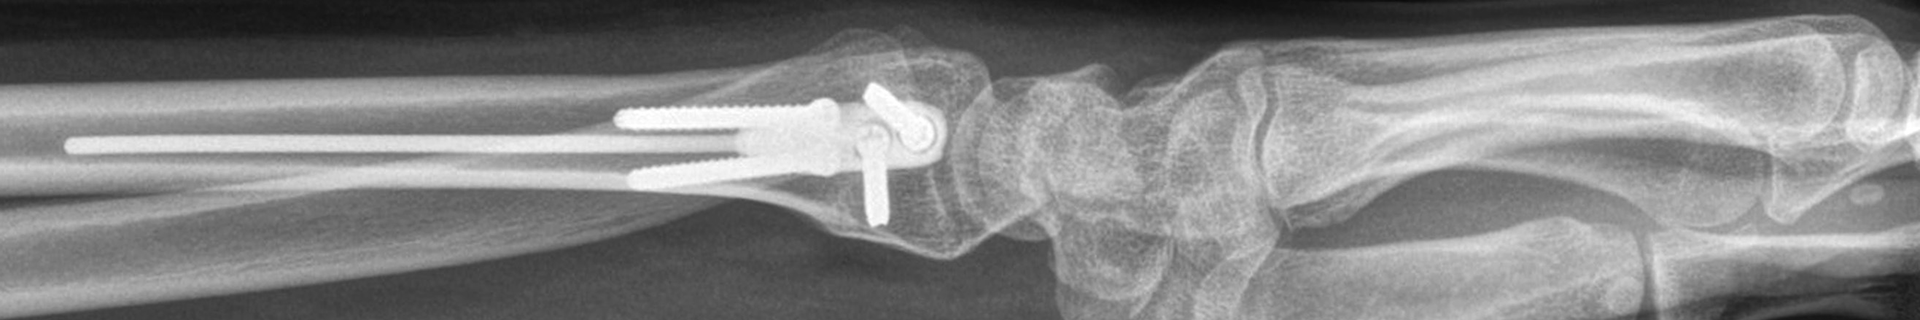

Approved by the AO in June 2022, the DRIM-Nail is an innovative treatment option for patients with extraarticular distal radius fractures. The design, development and certification of this new intramedullary nailing implant originally grew from a multi-partner collaboration between DISRAD AG, a start-up founded at Balgrist University Hospital by the Balgrist Beteiligungs AG, the University of Zürich, the AO Technical Commission's Hand Expert Group, the AO's Innovation Funding, and 41medical.

Consistent with the AO TC’s ethos of harnessing innovation to improve patient care and outcomes, the new DRIM-Nail provides all the benefits of minimally invasive intramedullary fracture stabilization, including minimal trauma to the bone fragments and the protection of the adjacent soft tissue. This aims to achieve faster recovery, better and faster functional and cosmetic outcomes, and a lower economic burden compared to current treatment options.